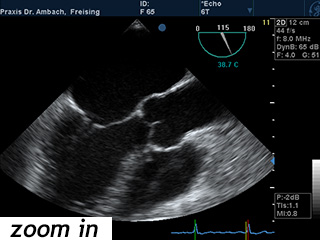

TEE

Die transösophageale Echokardiographie ist eine Ultraschalluntersuchung des Herzens über eine Sonde in der Speiseröhre ("Schluckecho"). Von hier lassen sich die Strukturen des Herzens sehr viel genauer als von außen darstellen. Klappenerkrankungen oder Defekte in der Herzscheidewand lassen sich damit gut beurteilen. Auch nach Schlaganfällen wird diese Untersuchungsmethode eingesetzt, um mögliche Blutgerinnsel im Herzen zu lokalisieren.